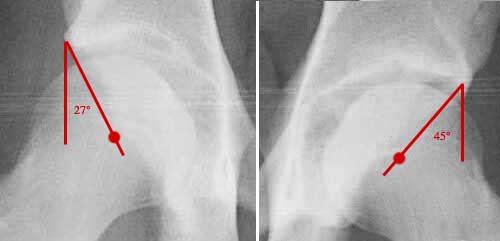

Lower Normal Limit of CE Angle in a 16 year old male.

25 degrees - (Michael Millis, AAOS Orthopaedic Grand Rounds, Series 1 Pediatrics, Hip Dysplasia)